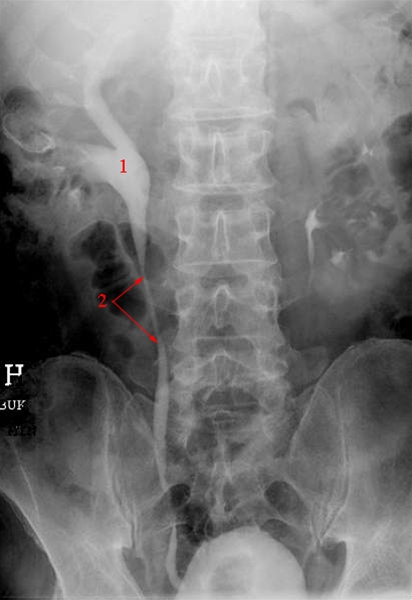

Urografi. Kontrastundersøgelsen viser et dilateret højre nyrebækken

1. Nyrebækken

2. Ureter (urinleder)